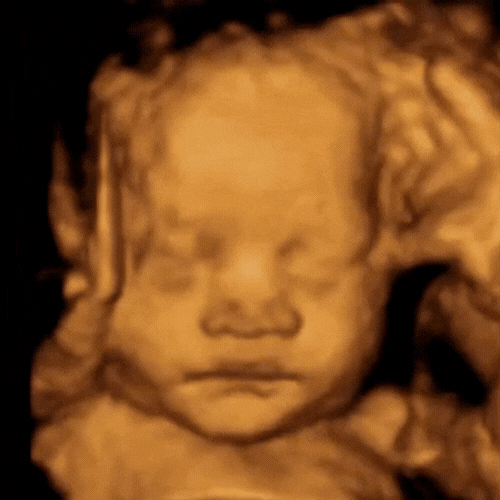

ScanSanctuary Client Scan Examples

Our state-of-the-art technology (GE Voluson Swift) is one of the most popular ultrasound machines for obstetric scanning. It features class leading 4D imaging as well as proprietary GE efficiency technologies. 3D/4D imaging modes, CrossXBeam and Speckle Reduction imaging assist with excellent accuracy.

3D / 4D Scan